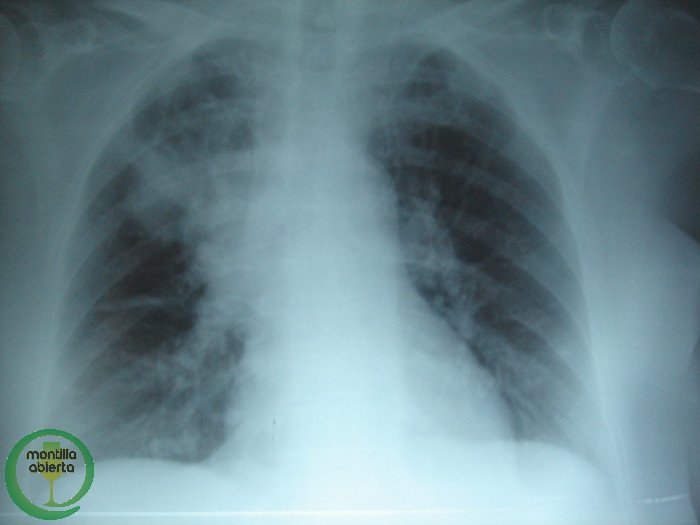

La Fibrosis Quística es una de las enfermedades genéticas graves más frecuentes y se estima una incidencia en nuestro país entorno a uno de cada 5.000 nacimientos, mientras que una de cada 35 personas son portadoras sanas de la enfermedad. Es una enfermedad crónica de origen genético que afecta a diferentes órganos, sobre todo pulmones y páncreas. En los últimos años se ha avanzado mucho en el conocimiento y tratamiento de la enfermedad pero, a pesar de eso, sigue siendo una patología sin curación.